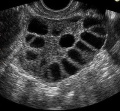

הרעיון בביצוע IVM הוא שאיבה של ביצית מזקיקים אנטרלים בהם מצויות ביציות אשר השלימו את מרבית ההבשלה שלהן. אחד היתרונות בשאיבת זקיקים אלו הנה הימצאותם הקבועה בשחלה, כך שניתן לבצע את השאיבה ללא קשר למחזור, ללא צורך בגירוי שחלתי ואף מספר פעמים במהלך מחזור אחד[2]. שאיבת הביצית גם בשלב של זקיק קטן, מאפשרת קבלת ביצית שלאחר הבשלה בת כ-36 שעות במעבדה, תניב ביצית בשלה. ביצית זו איננה שונה מבחינה מורפולוגית, לא בגודלה ולא במאפייניה החיצוניים מביצית הנשאבת מזקיק טרום ביוצי. לביצוע IVM ניתן לשאוב ביציות מזקיקים אנטרלים בגודל 2 מ"מ ומעלה [2].

- זמינות הזקיקים - ההערכה היא כי כ-10-20 זקיקים אנטרלים גדלים לשלב טרום ביוצי בכל מחזור[3]. לאחרונה דווח כי בכל מחזור באישה קיימים 2-3 גלים של התפתחות פוליקולרית, על פי עדויות שנמצאו במעקב על שמע יומי. ממצא זה מעלה את מספר הזקיקים אנטרלים הזמינים לשאיבה [5, 4]. השערה זו מתבססת על העובדה כי ביציות לא בשלות אשר נשאבו מזקיקים לא דומיננטיים, הבשילו במעבדה, הופרו, ואף הובילו להריון ולידה [6]. יחד עם זאת, במחזורי IVM חשוב למנוע את הביוץ של הזקיק המוביל, ולכן הניסיון מראה כי ניתן לתת hCG כאשר הזקיק המוביל מגיע ל-12 מ"מ, כדי למנוע את האטרזיה של הזקיקים הקטנים. חלק מהביציות הנשאבות בשלב זה מהזקיק המוביל יהיו בשלות. חשוב להדגיש כי הבשלת ביציות עד לשלב האנטרלי המוקדם מתרחשת כל הזמן וללא תלות בגונדוטרופינים. לכן ניתן למצוא ולשאוב זקיקים אלו ללא קשר למחזור, ואף מספר פעמים באותו מחזור [7].

כמו בכל התערבות רפואית הצלחת הטיפול תלויה בבחירה נכונה של המטופלות. קיים קשר ישיר בין הצלחת הטיפול למספר הביציות הלא בשלות הנשאבות. אחד הפרמטרים המשמשים לניבוי ההצלחה הינו מספר הזקיקים בתחילת המחזור - AFC (Antral follicular count). נשים עם 20 זקיקים או יותר בתחילת המחזור הינן בעלות סיכוי טוב להצלחת התהליך.

- נשים עם שחלות פוליציסטיות - זו הקבוצה המרכזית היכולה ליהנות מטיפולי IVM. מקובל להציע לאישה ביצוע IVM כאשר יש לה AFC של 20 זקיקים ומעלה.

- פרוטוקולים להכנת השחלות לשאיבת הזקיקים - ניתנת לביצוע במספר דרכים. בכל המקרים מוזמנת המטופלת לביצוע בדיקות דם ובדיקת על קול (אולטראסאונד) בימים 2-3. למחזור. בעל קול זה מבוצעת הערכת מספר הזקיקים האנטרלים (AFC) וגודלם. בשלב זה ניתן להתחיל גירוי הורמונלי קל בעזרת FSH למשך 3 ימים או להימנע ממתן הורמונים כלל. בימים 6-8 מבוצע על קול שני, בו נבדקים שוב כל הפרמטרים שהוזכרו לעיל. נהוג לתת hCG כאשר הזקיק המוביל בגודל של 12-16 מ"מ כדי להגדיל את הסיכויים לקבלת ביצית בשלה. בכל מקרה תנאי למתן הכוריגון הנו עובי רירית של 6 מ"מ ומעלה. במידה והרירית איננה בעובי המתאים, מחכים 3 ימים וחוזרים על העל קול כעבור 3 ימים. ניתן להוסיף אסטרוגן או HMG (Human menopausal gonadotropin) בשלב זה על מנת לעזור בבניית הרירית. במחקר רנדומלי שפורסם לאחרונה [9] וכלל 400 מטופלות, בוצעה השוואה בין פרוטוקולי טיפול שונים. במחקר זה נבדקו תוצאות הטיפול ב-4 קבוצות שונות: קבוצה ללא טיפול כלל ב-FSH ו-hCG, קבוצה שטופלה ב-hCG בלבד, קבוצה שטופלה ב-FSH בלבד וקבוצה שטופלה ב-FSH ו-hCG. תוצאות המחקר הראו יתרון ברור ומובהק בשיעור ההריונות בנשים שטופלו ב-FSH ו-hCG ביחס לכל הקבוצות האחרות. כמו כן נצפתה עליה בשיעור הביציות הבשלות בכל הקבוצות שטופלו ב-hCG. תרומת מתן hCG לעליה בשיעור ביציות בשלות נצפתה גם במחקרים נוספים. כאשר לא ניתן גירוי הורמונלי מקדים עם FSH, אחוז ההריונות היה גבוה יותר בקבוצה שלא קיבלה hCG

- פעולת שאיבת הביציות - השאיבה מבוצעת בד"כ בין ימים 10-14 למחזור, בהרדמה מקומית, ספינלית או כללית. הזרקה מקומית של מאלחש מקומי לקירות הנרתיק מפחיתה את אי הנוחות של הדקירות החוזרות. השאיבה מבוצעת תחת הנחיית על שמע עם מחט 19G, כאשר את תת הלחץ מורידים ל- 7.5kPa (85-100 מ"מ כספית). הנוזל הפוליקולרי נשאב למבחנות המכילות 0.9% Saline, עם IU/mL 2 הפרין. בכדי לשפר את יכולת איתור הביציות מבצעים סינון של נוזל השאיבה לאיתור ביציות נוספות. משך השאיבה ארוך יותר משאיבה ממוצעת של IVF כיוון שחשוב מאוד להקפיד לשאוב את כל הזקיקים הנצפים בעל שמע. שימוש במכשיר על שמע בעל דיוק גבוה תורם לשיפור ההצלחה